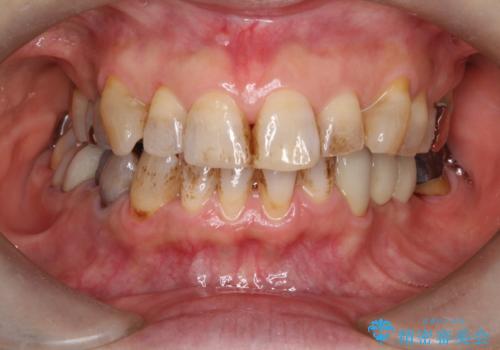

エアーフローでお茶による着色を除去

- 矯正治療後、定期的にクリーニングを受けている方ですが、暫く来院が空いてしまい、着色が酷くなっていました。

リテーナーを付けたまま、お茶を飲む事が多かったのが原因と思われます。

着色だけではなく、歯石やバイオフィルム等、不要な物を取っていく施術となります。

知覚過敏が心配な方も受けられるクリーニングです。